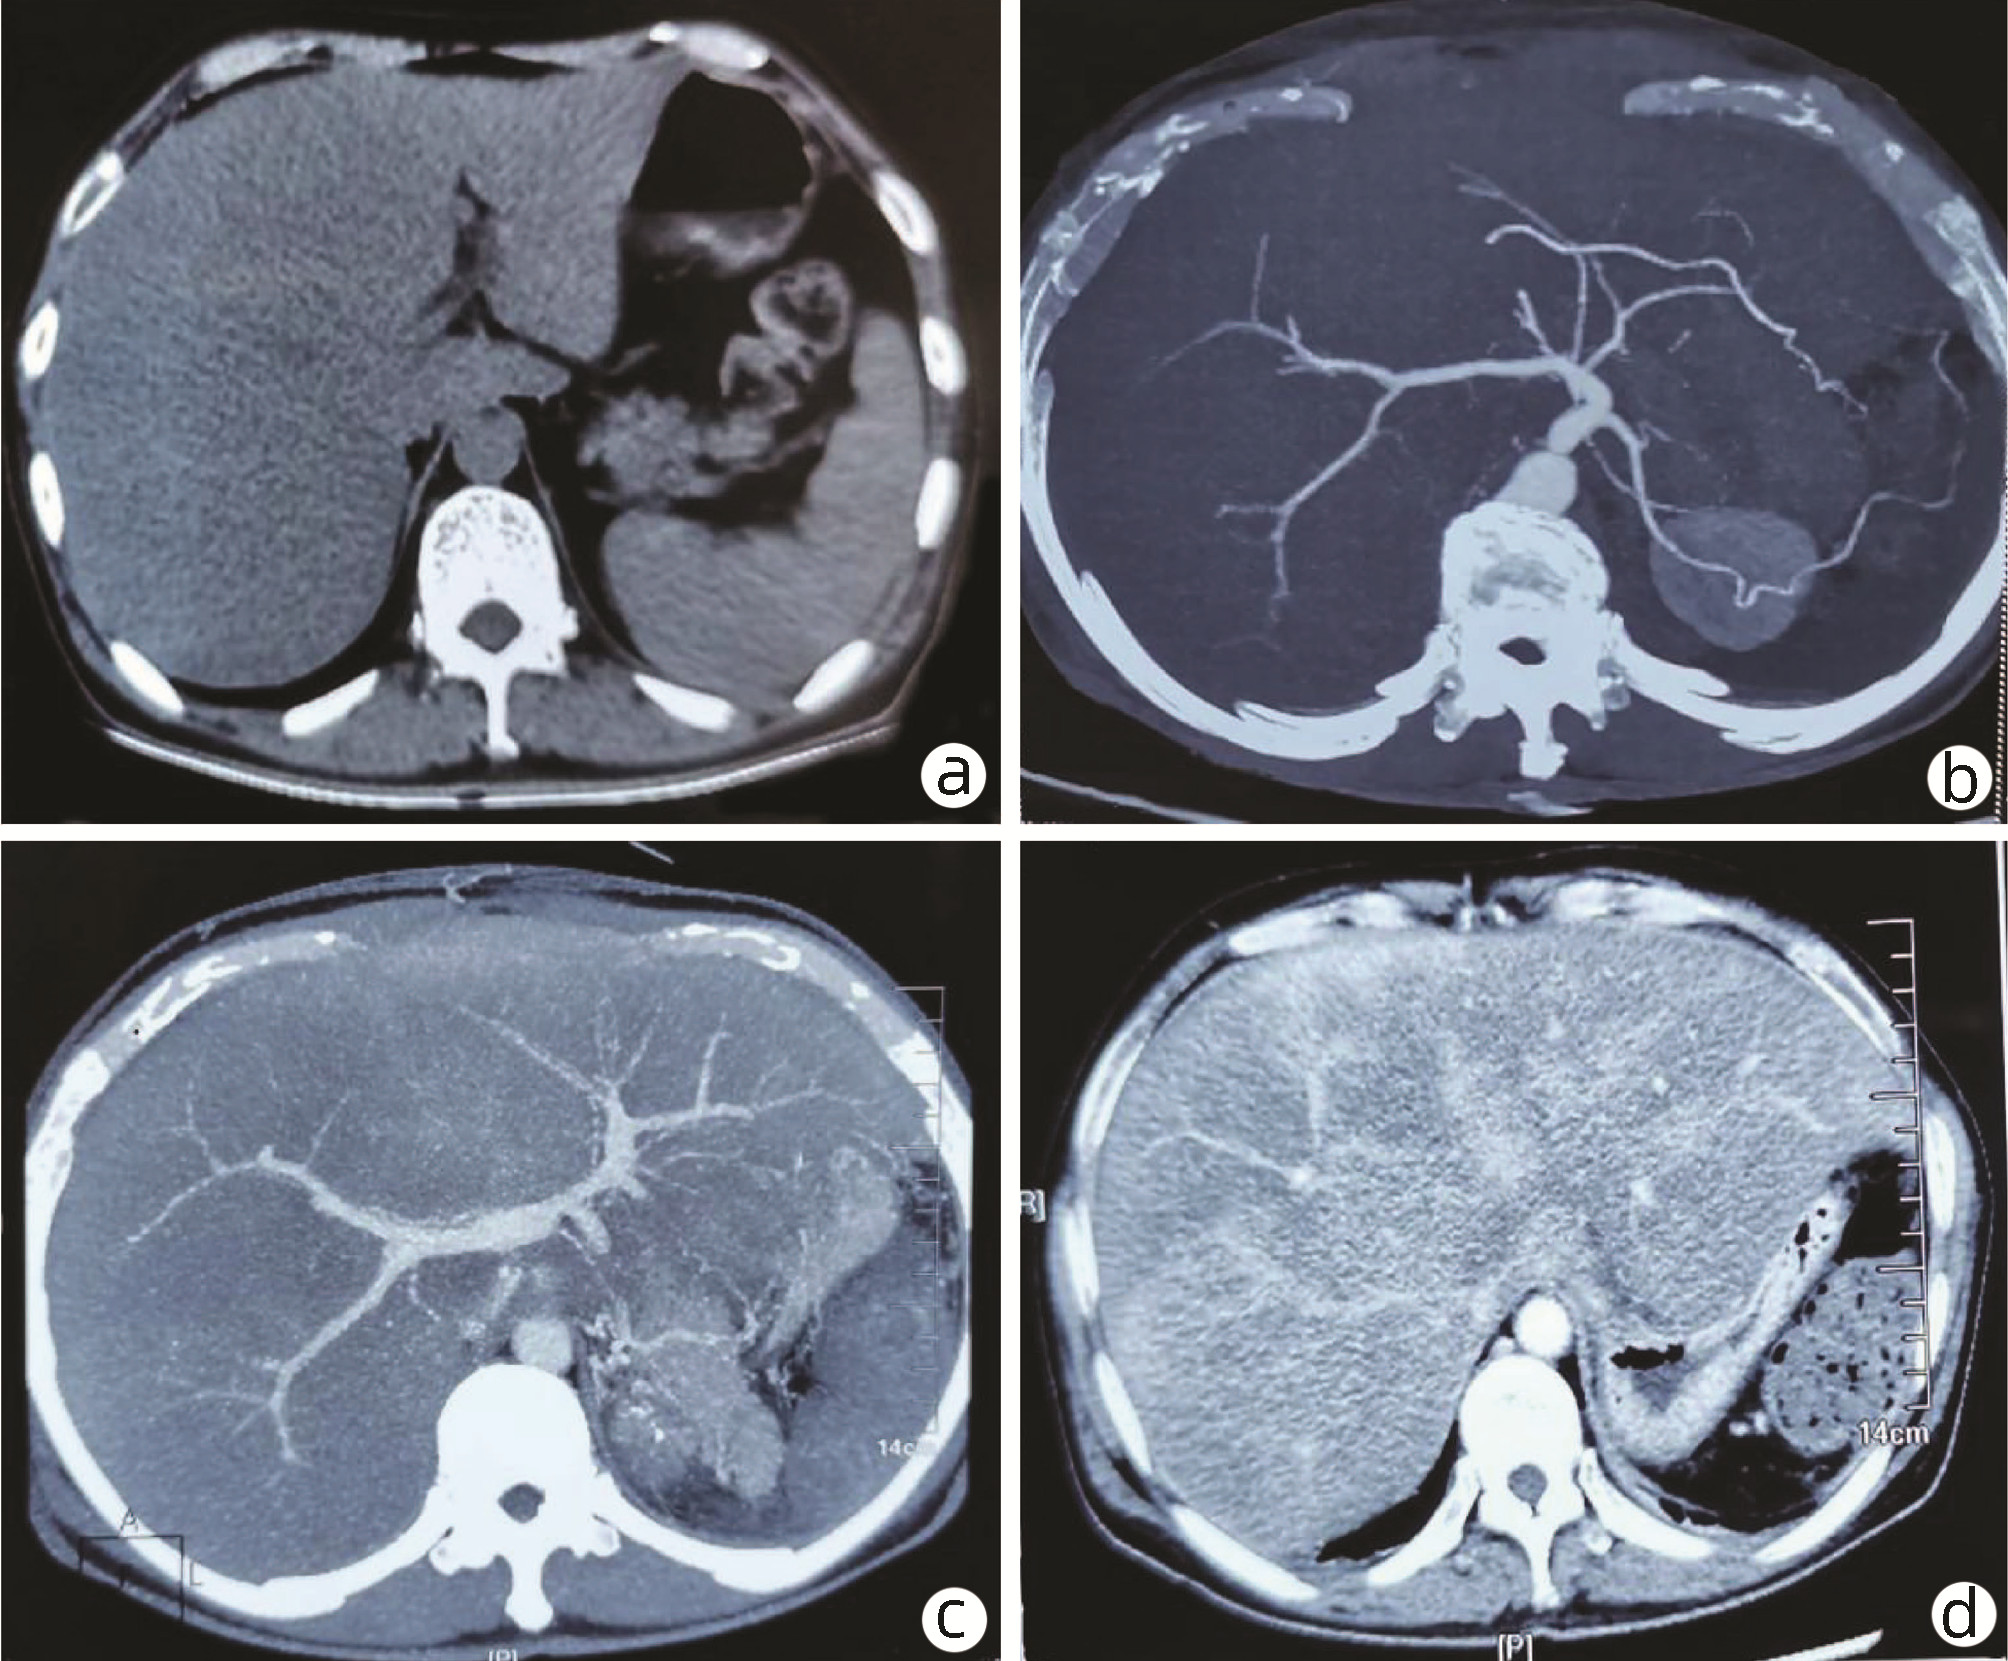

胰尾部神经鞘瘤1例报告

摘要(667) HTML (273) PDF (3067KB)(65)